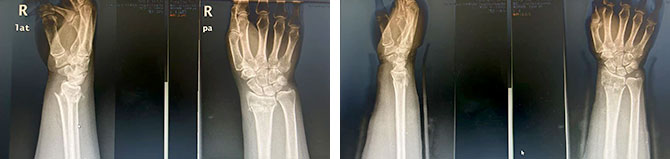

成人桡骨远端骨折(伸直型)

复位前 复位后